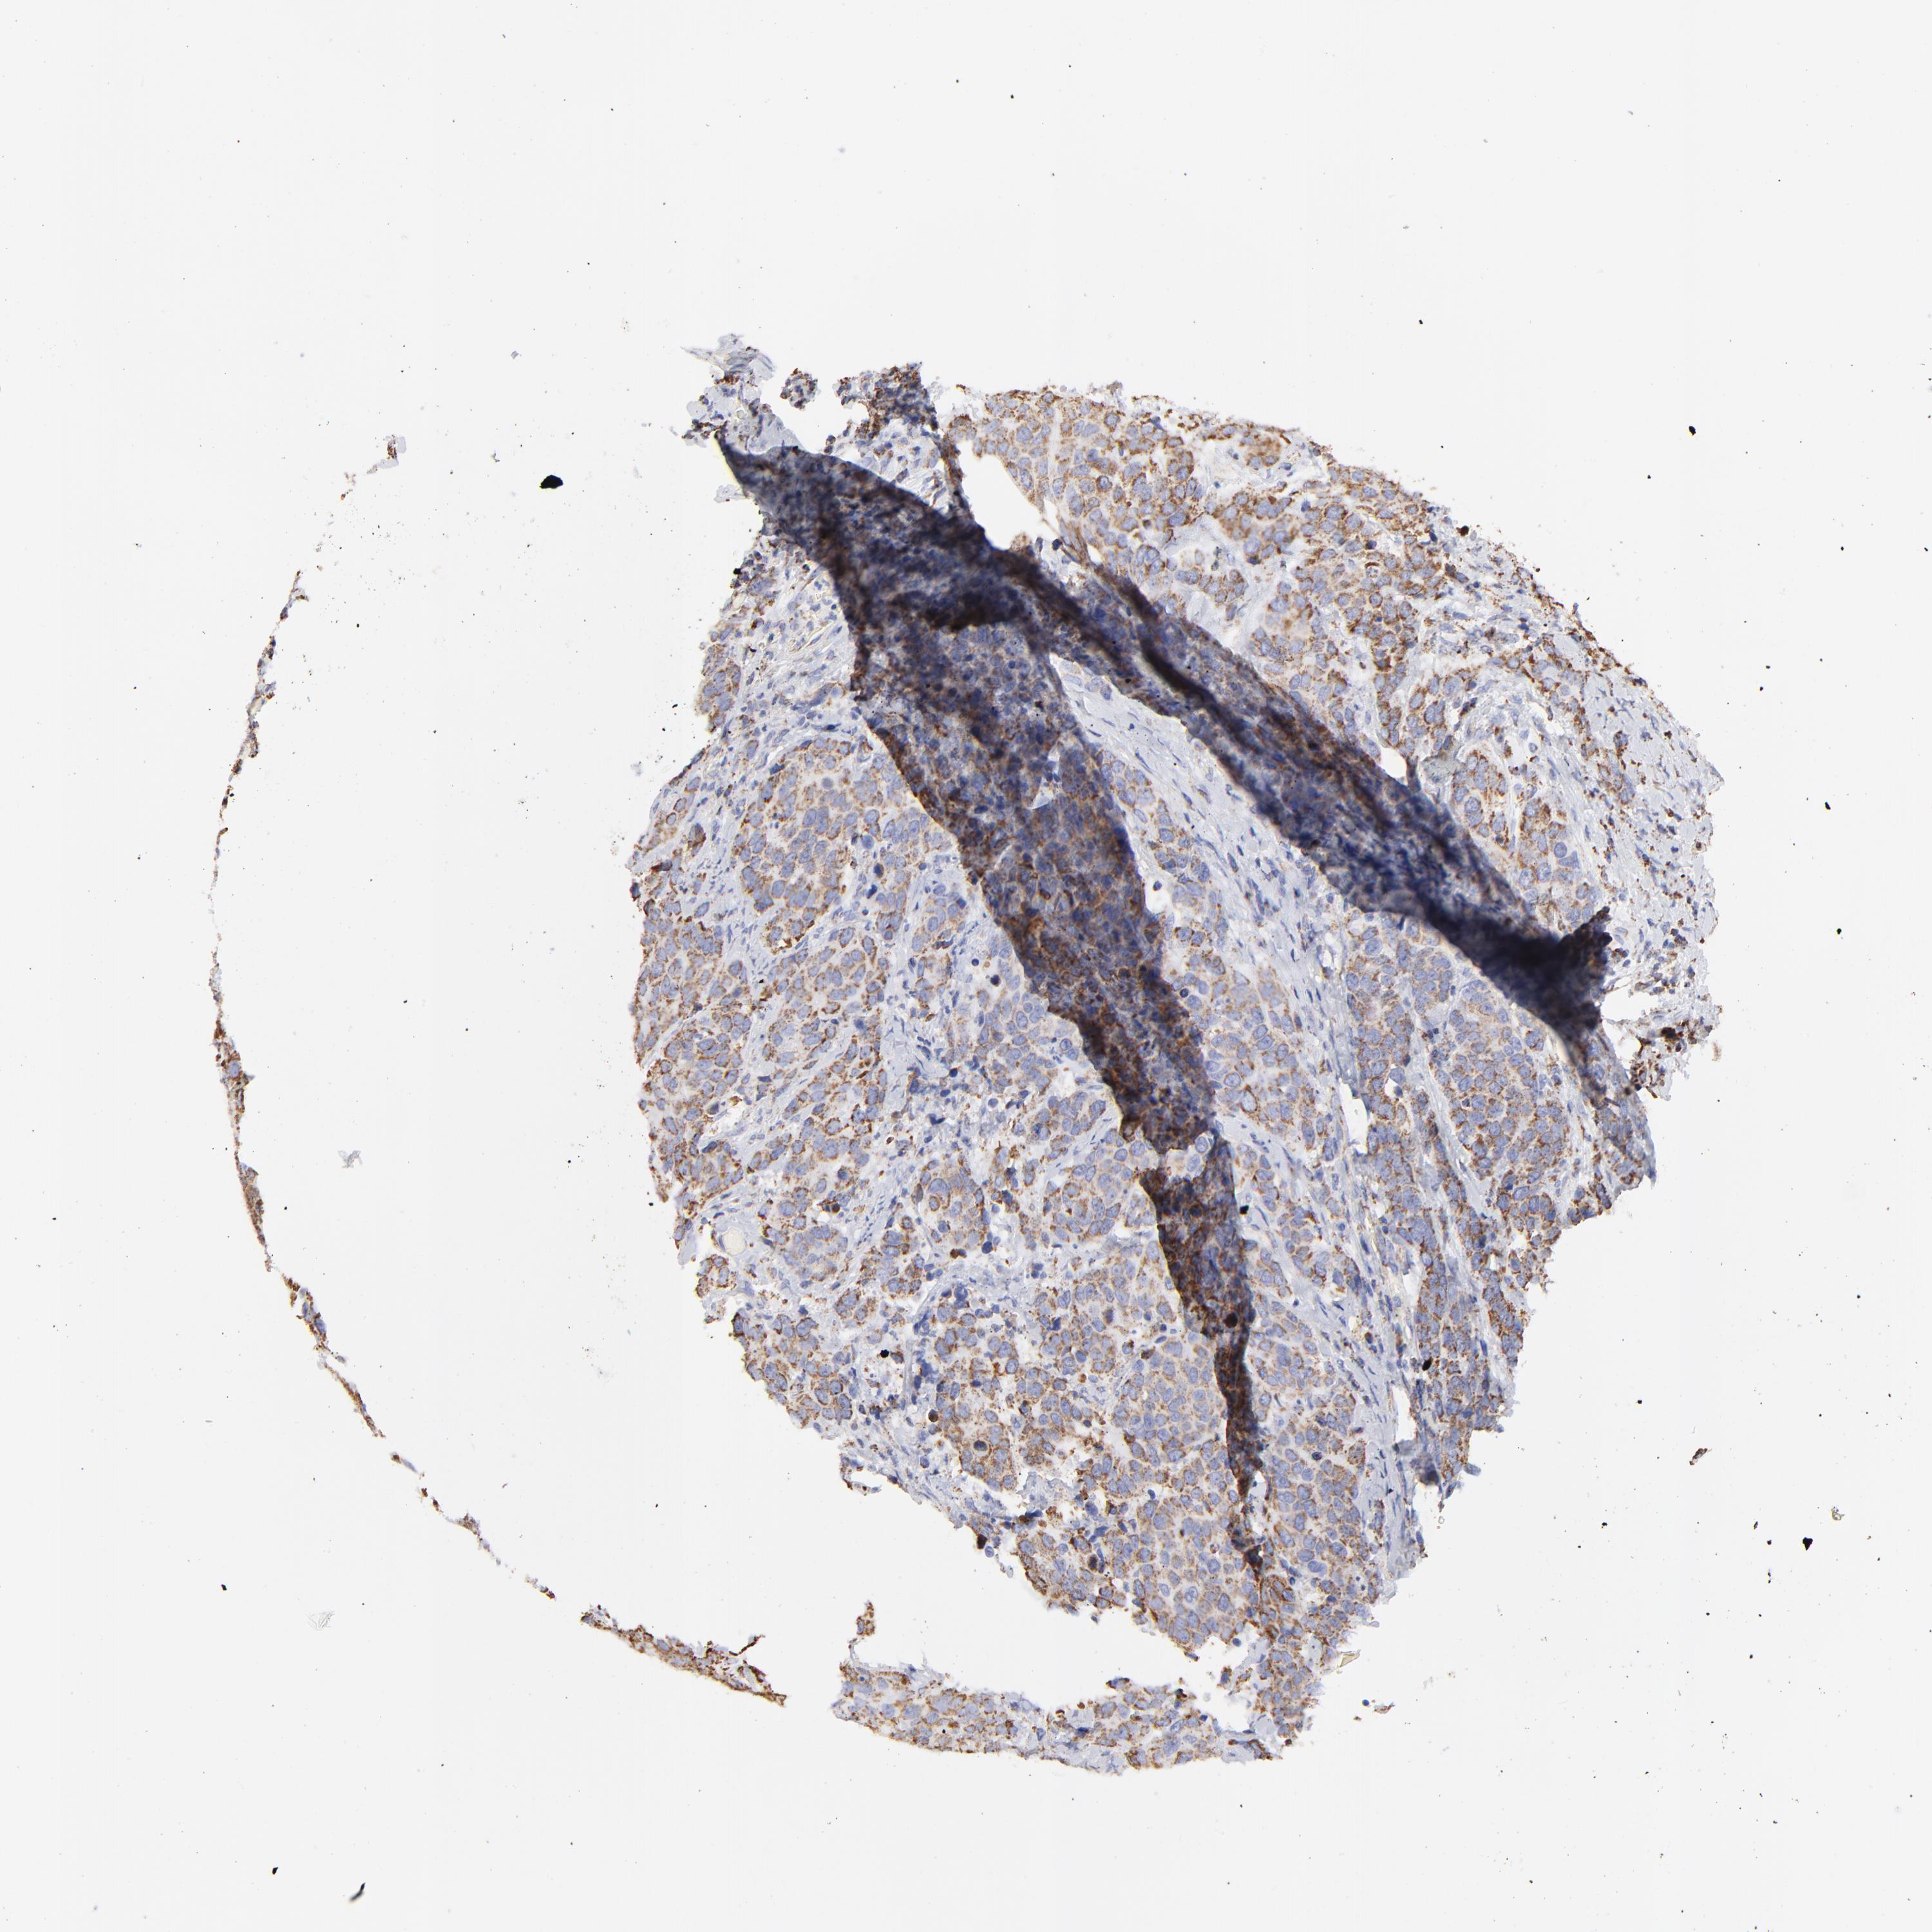

CERVICAL CANCER - Protein expressioni

A mouse-over function shows sample information and annotation data. Click on an image to view it in a full screen mode. Samples can be filtered based on level of antibody staining by selecting one or several of the following categories: high, medium, low and not detected. The assay and annotation is described here.

Note that samples used for immunohistochemistry by the Human Protein Atlas do not correspond to samples in the TCGA dataset.

Antibody stainingi

Antibody staining in the annotated cell types in the current human tissue is reported as not detected, low, medium, or high, based on conventional immunohistochemistry profiling in selected tissues. This score is based on the combination of the staining intensity and fraction of stained cells.

Each image is clickable and will lead to virtual microscopy that enables deeper exploration of all samples and also displays staining intensity scores, fraction scores and subcellular localization as well as patient and tissue information for each sample.

Antibody HPA002485

Antibody CAB004080

Staining

High

Medium

Low

Not detected

Intensity

Strong

Moderate

Weak

Negative

Quantity

>75%

75%-25%

<25%

None

Location

Nuclear

Cytoplasmic/membranous

Cytoplasmic/membranous,nuclear

Squamous cell carcinoma, NOS